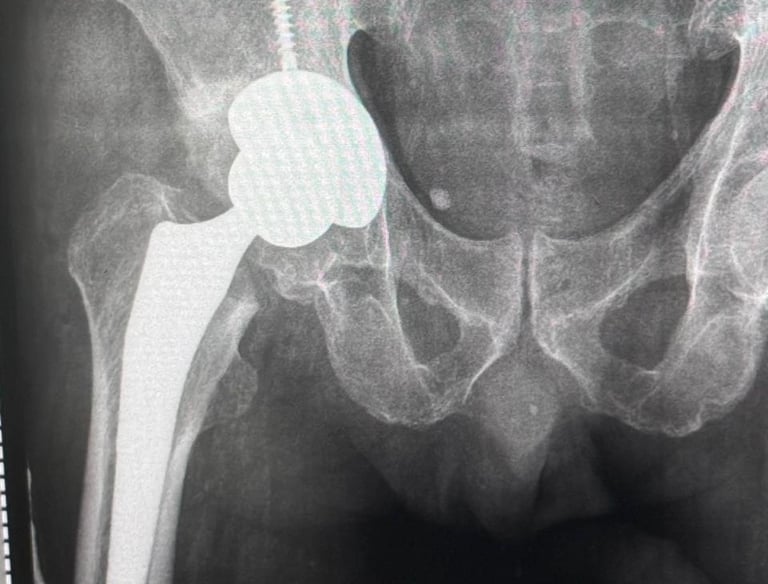

Cirugía de Cadera

Cirugías de reemplazo de articulaciones dañadas, como cadera o rodilla, para restaurar la movilidad y calidad de vida.